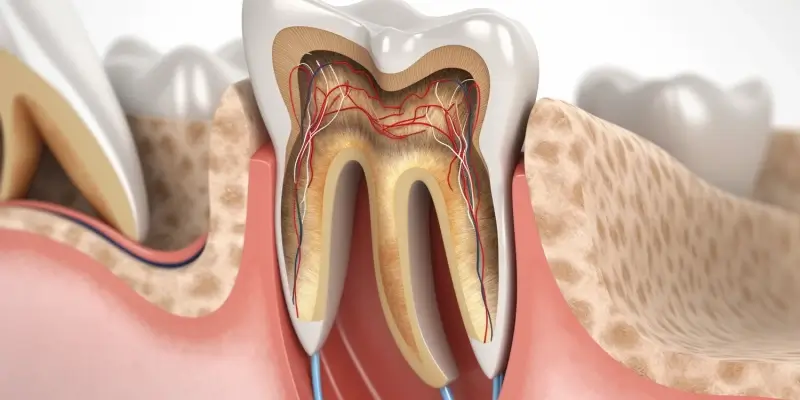

Endodoncja, czyli dziedzina stomatologii zajmująca się leczeniem chorób miazgi zęba i tkanek okołowierzchołkowych, stawia przed lekarzami ogromne wyzwania. Miazga, pełna naczyń krwionośnych i nerwów, jest niezwykle wrażliwa na uszkodzenia mechaniczne, urazy, a przede wszystkim na infekcje bakteryjne. Gdy bakterie przedostaną się do wnętrza zęba, na przykład przez głęboki ubytek próchnicowy, pęknięcie szkliwa czy uraz, mogą doprowadzić do zapalenia miazgi, a w konsekwencji do jej obumarcia. Nieleczony stan zapalny rozprzestrzenia się dalej, atakując tkanki otaczające korzeń zęba, co może prowadzić do powstawania ropni i utraty kości. Leczenie kanałowe w Szczecinie stanowi w takich przypadkach ostatnią deskę ratunku, pozwalającą na uratowanie naturalnego zęba, uniknięcie bolesnych ekstrakcji i skomplikowanych zabiegów protetycznych.

Decyzja o konieczności podjęcia leczenia kanałowego nie zapada pochopnie. Stomatolodzy w Szczecinie, podobnie jak ich koledzy po fachu w całym kraju, kierują się szeregiem objawów klinicznych i wyników badań diagnostycznych. Podstawowym wskazaniem do przeprowadzenia leczenia kanałowego jest nieodwracalne zapalenie miazgi zębowej. Objawia się ono zazwyczaj silnym, samoistnym bólem zęba, który może nasilać się w nocy lub pod wpływem bodźców termicznych, takich jak zimno czy gorąco. Ból ten jest zazwyczaj tępy i pulsujący, a jego lokalizacja może być trudna do precyzyjnego określenia.

Kolejnym sygnałem ostrzegawczym jest martwica miazgi, która może być wynikiem nieleczonego stanu zapalnego, urazu mechanicznego lub długotrwałego nacisku wywieranego na ząb. W przypadku martwicy miazgi ból może ustąpić, co jest mylące dla pacjenta. Jednak proces zapalny wewnątrz zęba nadal postępuje, prowadząc do rozwoju zmian w tkankach okołowierzchołkowych. Nierzadko towarzyszy temu zmiana zabarwienia korony zęba na szarawy lub brunatny odcień. Zęby martwe są bardziej kruche i podatne na złamania.

Specjaliści endodonci w Szczecinie zwracają również uwagę na obecność zmian zapalnych w obrębie wierzchołka korzenia zęba. Mogą one manifestować się jako bolesność przy nagryzaniu, obrzęk dziąsła, a nawet przetoka ropna, z której okresowo sączy się treść ropna. Zmiany te są widoczne na zdjęciach rentgenowskich, które stanowią nieodzowne narzędzie diagnostyczne w leczeniu kanałowym. Zęby po urazach, nawet jeśli początkowo nie odczuwamy bólu, również wymagają szczególnej uwagi i obserwacji, ponieważ uszkodzenie miazgi może ujawnić się z opóźnieniem.

Nowoczesne leczenie kanałowe, nazywane również leczeniem endodontycznym, to złożony proces wymagający precyzji, cierpliwości i odpowiedniego zaplecza technologicznego. Proces ten rozpoczyna się od szczegółowej diagnostyki, która obejmuje badanie kliniczne pacjenta, wywiad dotyczący dolegliwości bólowych oraz wykonanie zdjęć rentgenowskich, często w technologii cyfrowej, która pozwala na uzyskanie wysokiej jakości obrazu przy zminimalizowanej dawce promieniowania. W przypadku bardziej skomplikowanych przypadków, lekarze w Szczecinie mogą zlecić tomografię komputerową (CBCT), która daje trójwymiarowy obraz struktur zęba i otaczających tkanek, umożliwiając dokładną ocenę anatomii kanałów korzeniowych.

Kolejnym etapem jest przygotowanie pola zabiegowego. Ząb jest izolowany od reszty jamy ustnej za pomocą koferdamu – specjalnej lateksowej osłony. Pozwala to na utrzymanie sterylnych warunków w polu operacyjnym, zapobiega dostawaniu się śliny i bakterii do kanałów korzeniowych, a także chroni pacjenta przed przypadkowym połknięciem drobnych narzędzi czy płynów płuczących. Następnie lekarz wykonuje dostęp do komory miazgi, usuwając martwą lub zainfekowaną tkankę.

Kluczowym etapem jest opracowanie kanałów korzeniowych. Lekarz używa specjalistycznych narzędzi, często maszynowych, wykonanych z elastycznych stopów niklowo-tytanowych, które pozwalają na precyzyjne oczyszczenie i poszerzenie kanałów, nawet jeśli mają one nietypowy kształt. Długość kanałów jest precyzyjnie mierzona za pomocą endometru, a cały proces jest często wspomagany przez mikroskop zabiegowy, który pozwala na powiększenie pola zabiegowego i uwidocznienie nawet najmniejszych szczegółów anatomicznych.

Po mechanicznym oczyszczeniu kanałów następuje ich dezynfekcja. Stosuje się do tego celu specjalne płyny płuczące, takie jak podchloryn sodu czy roztwór EDTA, które mają za zadanie usunąć pozostałe tkanki, bakterie i produkty ich przemiany materii. Płukanie jest często wspomagane przez aktywację ultradźwiękami lub podczerwienią, co zwiększa skuteczność dezynfekcji. Po dokładnym osuszeniu kanałów następuje ich wypełnienie.

Współczesne metody wypełniania kanałów korzeniowych wykorzystują gutaperkę – materiał biokompatybilny, który jest plastyczny pod wpływem ciepła. Gutaperka jest umieszczana w kanałach wraz z uszczelniaczem, tworząc szczelne wypełnienie, które zapobiega ponownemu zainfekowaniu zęba. Po wypełnieniu kanałów, odbudowuje się koronę zęba. W zależności od stopnia zniszczenia, może to być wypełnienie kompozytowe, nakład, a w trudniejszych przypadkach nawet korona protetyczna. Cały zabieg, choć czasochłonny, jest zazwyczaj bezbolesny dzięki zastosowaniu skutecznego znieczulenia miejscowego.

Nowoczesny mikroskop zabiegowy jest nieocenionym narzędziem w rękach endodonty. Pozwala on na znaczące powiększenie pola zabiegowego, co umożliwia precyzyjne uwidocznienie drobnych struktur anatomicznych kanałów korzeniowych, wykrycie dodatkowych kanałów, które mogłyby zostać przeoczone, a także dokładne oczyszczenie i wypełnienie całego systemu kanałowego. To właśnie dzięki takiemu powiększeniu i precyzji możliwe jest skuteczne leczenie nawet najbardziej skomplikowanych przypadków.

Dzięki mikroskopowi stomatolog może precyzyjnie zlokalizować i opracować wszystkie ujścia kanałów korzeniowych, nawet te dodatkowe, które często są przyczyną niepowodzeń leczenia. Pozwala to również na dokładne usunięcie zainfekowanej tkanki, kontrolę szczelności wypełnienia kanałów oraz wykrycie i naprawę pęknięć korzenia. Zastosowanie mikroskopu znacząco podnosi przewidywalność leczenia i zmniejsza ryzyko powikłań, co jest szczególnie ważne w przypadku skomplikowanych przypadków leczonych w Szczecinie.

Dzięki możliwości uzyskania nawet 40-krotnego powiększenia pola zabiegowego, lekarz jest w stanie dostrzec najdrobniejsze detale anatomiczne kanałów korzeniowych. Pozwala to na dokładne wykrycie wszystkich ujść kanałów, w tym tych dodatkowych, często ukrytych w zakamarkach komory zęba, które są główną przyczyną niepowodzeń leczenia endodontycznego. Mikroskop umożliwia również precyzyjne usunięcie zainfekowanej tkanki, oczyszczenie kanałów z resztek miazgi i bakterii, a także skuteczne wypełnienie całego systemu kanałowego.

Jednym z kluczowych zastosowań mikroskopu w leczeniu kanałowym jest wykrywanie i opracowywanie tzw. kanałów dodatkowych, które często są wąskie, zakrzywione i trudne do zlokalizowania bez odpowiedniego powiększenia. Zaniedbanie nawet jednego takiego kanału może prowadzić do rozwoju infekcji i konieczności powtórnego leczenia kanałowego. Mikroskop pozwala również na skuteczne radzenie sobie z przypadkami, gdy w kanałach znajdują się złamane narzędzia endodontyczne lub inne ciała obce, które mogą blokować prawidłowe opracowanie i wypełnienie.